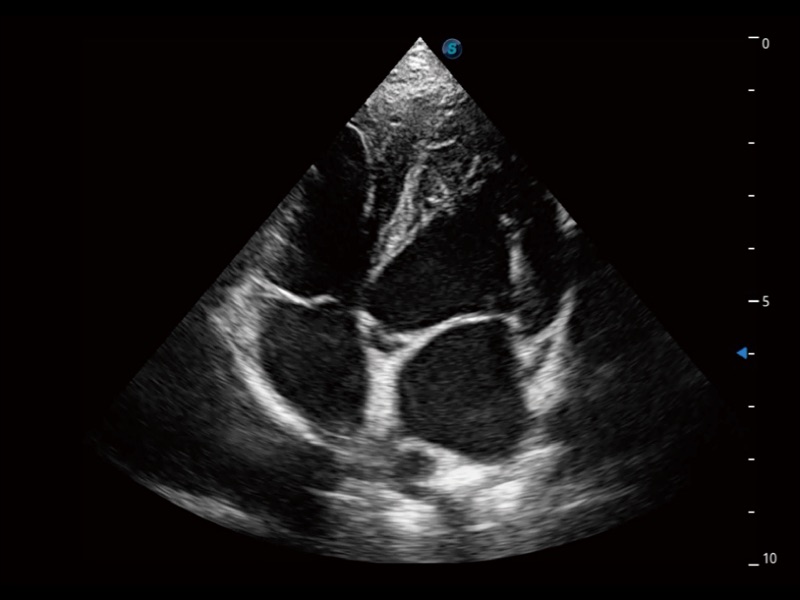

ProPet 70 进一步提升了微米成像算法,更加注重对基础原始图像的还原和保留,在有效减少斑点噪声、增强组织边界显示的同时,避免过度优化丟失真实的解剖信息。

通过360度任意调节3条M型取样线,在同一心动周期上观察心脏不同位置的运动曲线,得到准确的心功能测量数据,有效评估心肌运动及左心室功能。

实时用颜色表示心肌组织运动,观察和定量组织的运动情况,对快速检测与评估心肌的灌注和活性、电传导及心肌收缩和舒张功能等均能提供重要的诊断信息。